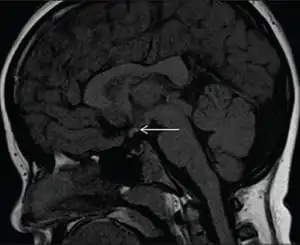

| Diagnostic method | MRI scan |

Pituitary stalk interruption syndrome (PSIS) is a congenital disorder characterised by the triad of an absent or exceedingly thin pituitary stalk, an ectopic or absent posterior pituitary and/or absent or hypoplastic anterior pituitary.[1][2]